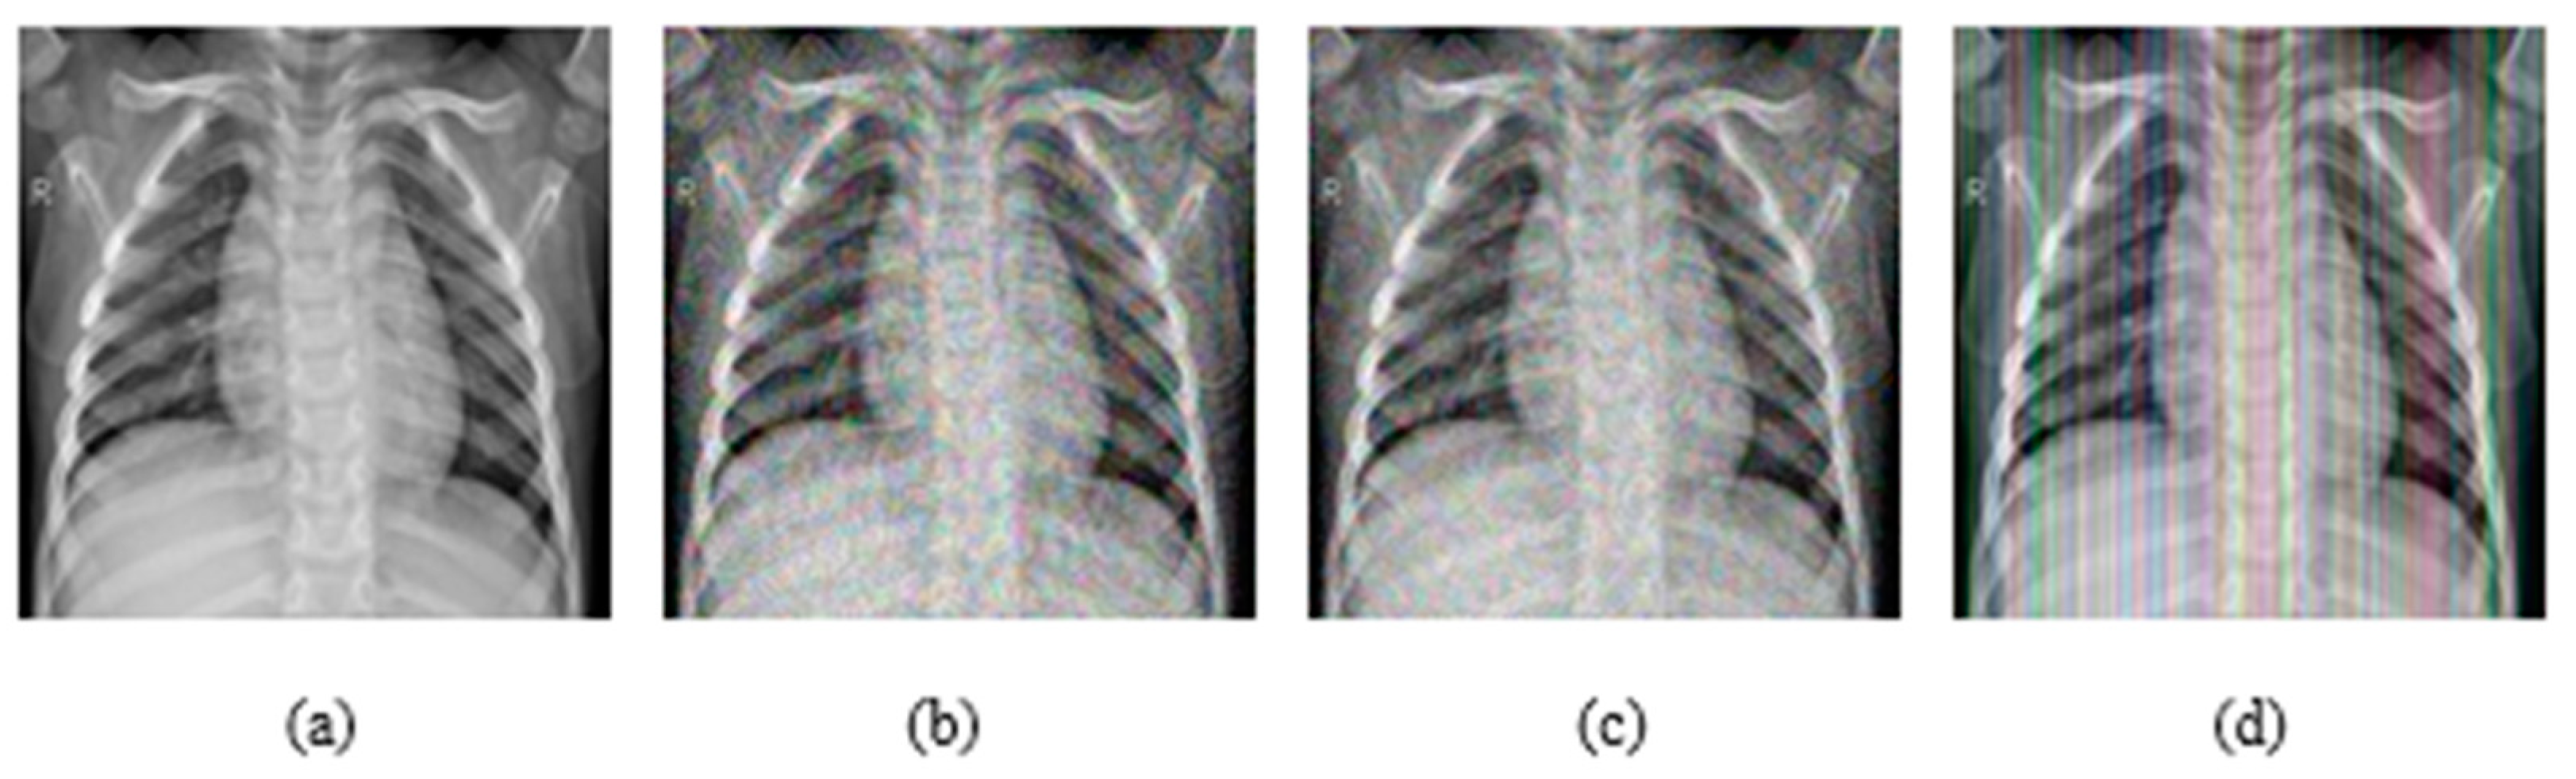

In addition, experiments were performed with FGSM, PGD, and Square Attack for ϵ values equal to 0.01, 0.03, 0.05, 0.07, 0.09, 0.12, and 0.15. In Figure 6, MRI with aforementioned attacks and ϵ = 0.01 are presented. The human eye cannot understand any difference between these images. In Figure 7, attacks with ϵ = 0.07 are depicted. Square Attack causes the biggest distortion compared to FGSM and PGD. However, small changes can be observed also in the other two attacks. In Figure 8, the ϵ value has been increased to 0.15, making the noise perceptible.

Figure 6.

(a) Initial Image, (b) FGSM attack with ϵ = 0.01, (c) PGD attack with ϵ = 0.01, (d) Square Attack with ϵ = 0.01.

Figure 7.

(a) Initial Image, (b) FGSM attack with ϵ = 0.07, (c) PGD attack with ϵ = 0.07, (d) Square Attack with ϵ = 0.07.

Figure 8.

(a) Initial Image, (b) FGSM attack with ϵ = 0.15, (c) PGD attack with ϵ = 0.15, (d) Square Attack with ϵ = 0.15.